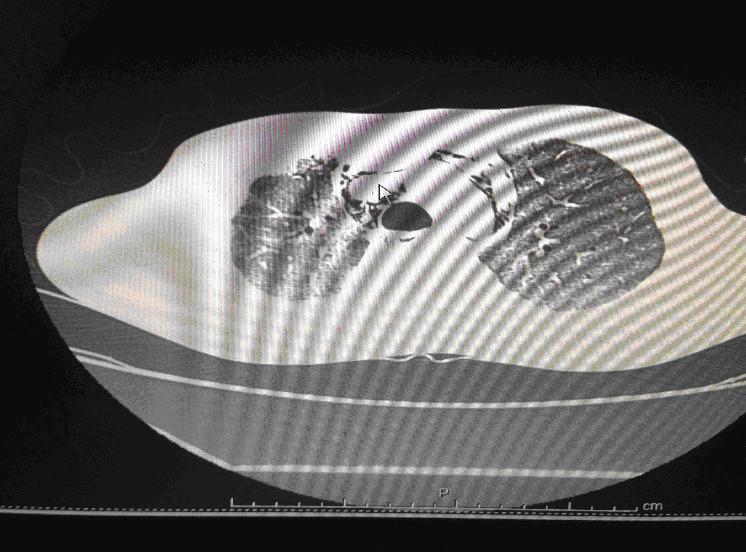

24 year old male, who is a K/C/O Embryonal Ca Testis- S/P Orchidectomy done 6 months back followed by chemotherapy with Bleomycin for 4 cycles, had presented with complains of cough since 1month and fever since 2 weeks. Associated breathing difficulty was also present and cough was productive. On arrival in the ED he was conscious ,oriented and talking .His vitals showed a HR of 125/min, BP of 90/60 and Saturation was 80%in Room Air. His RR was 35/min and was febrile. Work of breathing was greatly increased and bilateral coarse crepitations were present. Blood gases revealed Respiratory Acidosis. A trial of Non Invasive Ventillation (Bi PAP) was tried initially but failed. He was intubated immediately and put on pressure controlled ventilation.IV fluids were started and early antibiotics initiated. Initial CT Thorax showed features suggestive of Brochiolitis Obliterans organizing Pneumonia (BOOP).

Following admission in the Medical ICU, Bronchoscopy was done and started on IV steroids and higher End Antibiotics. His bronchial wash grew ESBL Klebsiella and Pseudomonas. His other organ functions were not deranged. Repeat CT Thorax was taken which showed ground glass opacities, septal thickening, traction bronchiectasis, pleural thickening which was all S/o Drug induced Toxicity-Bleomycin.

High-resolution computed tomography (HRCT) of the chest is more sensitive than chest radiography in identifying lung abnormalities in bleomycin-exposed patients. HRCT patterns usually reflect the underlying histopathology . Diffuse alveolar damage is associated with airspace consolidation and ground-glass opacities. Findings suggestive of end-stage fibrosis include extensive reticular markings, traction bronchiectasis, and honeycombing. Organizing pneumonia manifests as ground-glass opacities in a bilateral but asymmetric pattern or by airspace consolidation with a subpleural or peribronchial distribution. Organizing pneumonia may occasionally present as one or more nodular densities that may mimic tumor metastases.